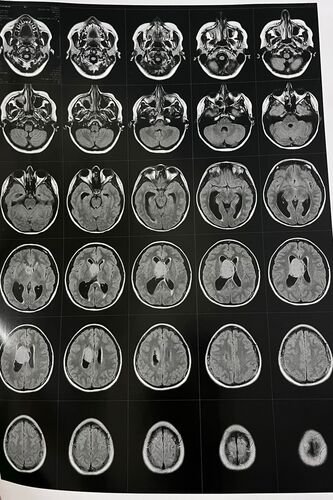

Estamos iniciando esta campanha com um único objetivo: arrecadar recursos para que a Nicoli possa realizar uma cirurgia delicada no cérebro. Recentemente, ela foi diagnosticada com um tumor cerebral, que requer avaliação especializada e procedimento cirúrgico com urgência.